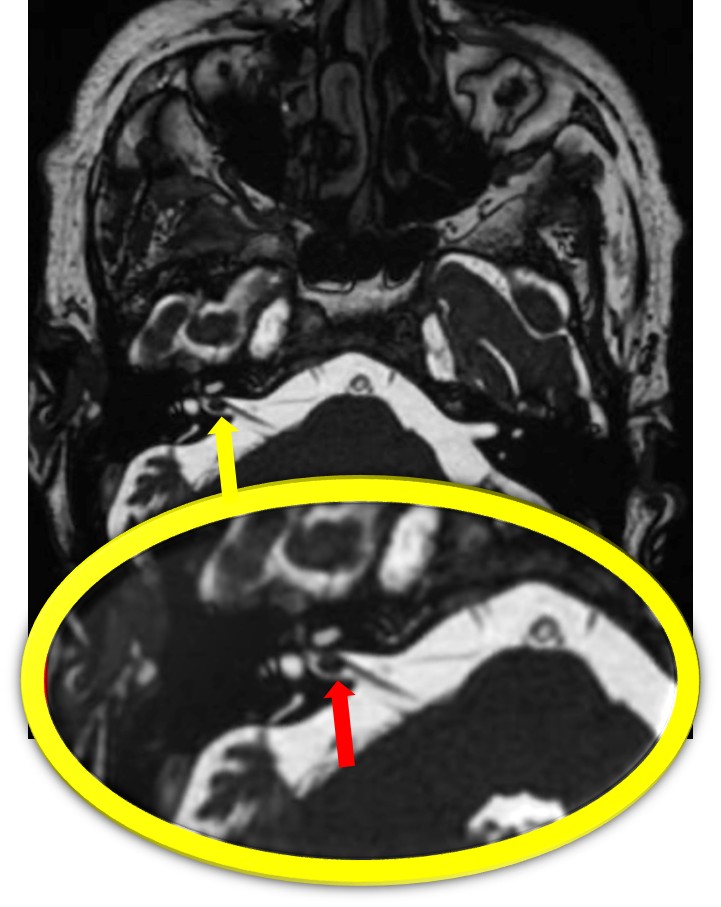

FIESTA同様、黒くなっているのが確認できる。

約2mmの病変も鮮明に描出